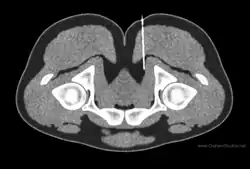

There are no specific or consistent radiological findings in patients with pudendal nerve entrapment.[33] Imaging cannot be used as evidence of a diagnosis of pudendal nerve entrapment,[16] but may be helpful to exclude other conditions (see: differential diagnosis).[33]

Magnetic resonance imaging or computed tomography are sometimes used. In people with unilateral pudendal entrapment in the pudendal canal, it is typical to see asymmetric swelling and hyperintensity affecting the pudendal neurovascular bundle.[53] The appearance on MRI may also be normal in pudendal neuralgia.[9]